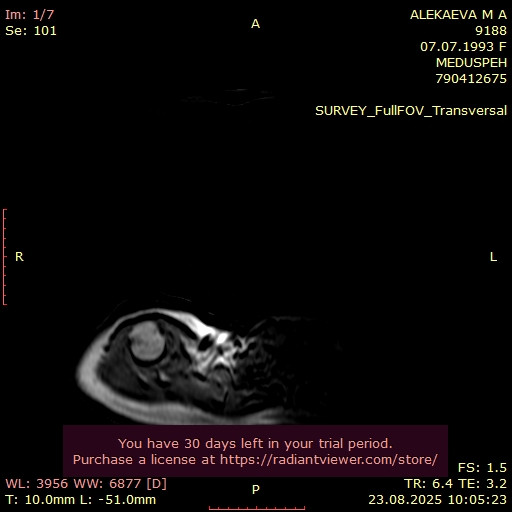

ПРОТОКОЛ МАГНИТНО-РЕЗОНАНСНОЙ ТОМОГРАФИИ Исследование выполнено в аксиальной, сагиттальной плоскостях, в T1W, T2W, PD, Головка правой плечевой кости имеет обычную конфигурацию и сочленяется с нормально развитой суставной ямкой. Суставные поверхности имеют относительно четко очерченные края. Суставная щель минимально сужена. Полость сустава содержит физиологическое скопление свободной жидкости. Определяются участки реконверсии костного мозга видимых костных структур. Акромиоклавикулярный сустав имеет обычную конфигурацию, отмечаются невыраженные дегенеративные изменения в виде неровностей контуров суставных поверхностей, краевых остеофитов; в полости сустава невыраженное скопление свободной жидкости; подакроминальные мягкие ткани имеют местами повышенный МР-сигнал, нельзя исключить проявления импиджмент синдрома, соотнести с клинико-анамнестическими данными. Сухожилие надостной мышцы типично расположено, определяется его невыраженное разволокнение, МР-сигнал местами повышен, целостность достоверно не нарушена. Сухожилие подостной мышцы типично расположено, убедительно не изменено. Сухожилие малой круглой мышцы, суставно-плечевые связки – без признаков повреждения. Сухожилие двуглавой мышцы определяется в типичном месте (в межбугорковой борозде), не изменено. По ходу сухожилия физиологическое скопление свободной жидкости. Сухожилие подлопаточной мышцы типично расположено, без убедительных признаков повреждения. Остальные мышцы, покрывающие плечевой сустав, имеют неизмененную интенсивность сигнала. Губа суставной впадины плечевого сустава невыраженно дегенеративно изменена, без убедительных МР-признаков повреждения. Заключение: МР-признаки начальных проявлений остеоартроза правого плечевого и акромиоклавикулярного сустава (1 ст), нельзя исключить проявления импиджмент синдрома (соотнести с клинико-анамнестическими данными). МР-картина невыраженных проявлений тендинопатии сухожилия надостной мышцы. Невыраженный синовит акромиоклавикулярного сустава. Рекомендовано: Консультация травматолога-ортопеда. При необходимости КТ для оценки костных структур / УЗИ.